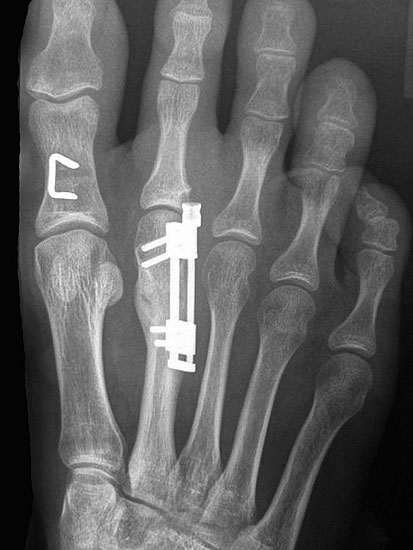

Das im Folgenden vorgestellte Operationsverfahren beschreibt die Kallusdistraktion von Metatarsalia nach den Prinzipien von Ilisarov 21 unter Verwendung eines internen, winkelstabilen Titan-Minifixateur (Klauser 2009). Der interne Distraktor ermöglicht während der Distraktions- und der Durchbauungsphase aufgrund seiner hohen Stabilität je nach Modell (18 mm, 23 mm) eine Verlängerung von bis zu 25 mm. Nach interner Anlage des Minifixateurs, meist lateral, kann über eine kontinuierliche Kallusdistraktion der Metatarsalebogen unter frühzeitiger Mobilisation im Gips oder Short-Walker rekonstruiert werden 15. Über einen interdigital und transcutan ausgeleiteten Aktivatorstab wird die Distraktion vom Patienten selber täglich morgens und abends durchgeführt. Zusätzlich vorliegende Strahlpathologien, wie zum Beispiel eine verkürzte Strecksehne oder ein kontraktes Metatarsophalangealgelenk können im Rahmen der Erstoperation ebenso therapiert werden wie z.B. ein Hallux valgus, ein Hallux valgus interphalangeus und/oder ein Digitus quintus varus (Klauser 2009). Nach Rekonstruktion des Metatarsalebogens wird in einem zweiten, kleinen Eingriff der Aktivatorstab über eine Spezialpinzette diskonnektiert und entfernt, wobei der Distraktor als interne Fixation belassen wird. Die Entfernung des Distraktors erfolgt in der Regel nach 9 – 12 Monaten, da es sich meist um angeborene kindliche Fehlbildungen handelt (Brachymetatarsie) und eine operative Intervention frühzeitig im Kindesalter erfolgen sollte (Klauser 2009).

• Dritter Eingriff: Materialentfernung (Minifixateur interne) bei vollständiger knöcherner Durchbauung, hierbei ist in seltenen Fällen eine Lösung von Verklebungen der Strecksehnen und des Metatarsophalangealgelenks erforderlich.

Der Autor überblickt 73 Rekonstruktionen der Brachymetatarsie mittels internem Distraktor und über 19 Verlängerungen von Metacarpalia oder Fingerphalangen bei posttraumatischen Deformitäten oder angeborenen Reduktionsdefekten bzw.  Aplasien.

Meist kam ein 18mm Minifixateur zur Anwendung und ausnahmslos wurde er lateral am Metatarsale implantiert. Bis auf das Metatarsale 5 wurden vom Autor alle weiteren Metatarsalia (MT1 – MT4) isoliert oder kombiniert verlängert. In 7 Fällen wurde eine simultane Verlängerung zweier Metatarsalia (2x MT1 und MT4, 4x MT3 und MT4, 1x MT2 und MT3) vorgenommen. Bei einem Großteil der Patienten musste eine Strecksehnenverlängerung entweder im Rahmen der Erstoperation oder im Rahmen der Aktivatorentkopplung vorgenommen werden. In neun Fällen (ausnahmslos bei Erwachsenen > 30 Jahre) sogar 2x sowohl während des Erst- als auch Zweiteingriffes. Annähernd regelhaft sind bei den eben genannten Eingriffen Arthrolysen des Metatarsophalangealgelenks des betroffenen Zehenstrahls erforderlich, da durch die Distraktionsverlängerung eine hohe Kompression auf das jeweilige Grundgelenk entsteht.